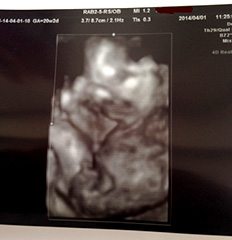

4月1日(火) 性別判明!

顔の前に手を当ててるらしい。目元は夫似?

今日の妊婦健診で性別がわかりました。お、お、お、男の子です~っ!!

素人目にも、股間にオチンチンらしき棒状の物体がはっきりと写り込み、しかも、すぎ丸は手でそれを触わっていたというアホ男児っぷり…。

それでも、“女の子な予感”を抱いていた私はにわかに信じがたく、どれくらいの確率なのか尋ねたところ、「確率もなにも、これだけ俺は男だってアピールしてるんだから間違いないよ(笑)」と先生。

夫宅のDVDプレイヤーを借りて、産院で録画した2Dと4Dの超音波DVDを初めて観賞。今までの検査がはっきり写っていて、両親も「これが頭?」「顔の表情までわかるのね」と喜んで観てくれた。

おまけに、先生と私の声までしっかり録音されていて(知らなかった!)、すぎ丸がおちんちんを触っていると指摘されたくだりは、一同大爆笑…。胎児の成長を家族みんなで分かち合えるなんて、文明の利器って素晴らしい!